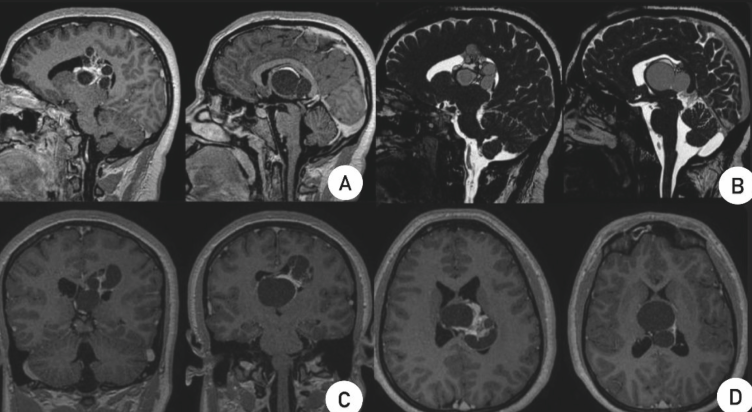

MATURE INTRACRANIAL TERATOMA: CASE REPORT

Por Dr. Chrystiano Fonseca Cardoso.

Intracranial terato- mas are rare germ cell tumors, accounting for approximately 0.5% of all intracranial tumors. They can be classified as mature, immature, or malignant, and are typically located along the midline of the brain, particularly around the third ventricle, pineal region, and suprasellar area.

Case Report: A 20-year-old female pa- tient presented with a history of seizures, hea- dache, nausea, vomiting, and diplopia. A cra- nial MRI revealed a multicystic lesion in the left lateral ventricle with ventricular dilation. Surgery was performed with an interhemis- pheric approach and partial resection of the lesion, confirming the diagnosis of a mature teratoma. The patient had a favorable recovery with no neurological deficits.